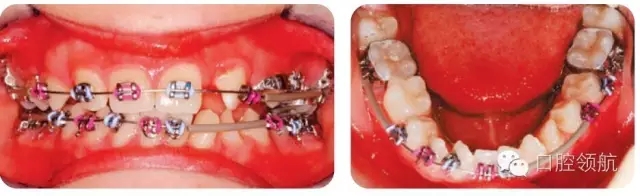

圖2.24中為何下頜有的牙齒未粘結(jié)托槽?

LL2和LL3幾乎扭轉(zhuǎn)90°,沒有足夠間隙改扭轉(zhuǎn)排齊。很難在扭轉(zhuǎn)牙的正確位置粘結(jié)托槽,所以在治療開始階段暫不納入,并用塑料套管支持弓絲,避免刺激軟組織。治療中推出間隙再排齊扭轉(zhuǎn)牙。

圖2.24

圖2.25中使用的是什么矯治方法?

圖2.25

● 0.018不銹鋼圓絲。

● 上頜右側(cè)用推簧推出前磨牙間隙。

● 前磨牙舌側(cè)粘結(jié)舌鈕,用橡皮鏈改扭轉(zhuǎn)。

● 橡皮鏈通過腭側(cè)的連接桿連接至UL6、UL5和UL4,加強固位。

● UL1、UR1和UR2連扎為一體,用橡皮鏈牽引UL2至正位,鄰接UL1,為UL3提供位置。